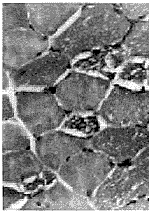

1.3 肌肉病理及电镜检查 15例均行肱二头肌或股四头肌肌肉活检。标本行苏木素-伊红染色、苏丹黑染色以及ATP酶染色、还原酶辅酶Ⅰ染色。15例患者苏木素-伊红染色骨骼肌肌纤维内均有大量脂滴沉积,呈圆形空泡,部分相互融合(图1)。苏丹黑染色显示肌纤维内充满黑色空泡,为脂肪滴(图2)。ATP酶染色显示脂滴沉积以Ⅰ型肌纤维为主。电镜检查: 15例病人于肌原纤维间或质膜下见脂滴明显增多,成串或成簇堆积(图3),多位于线粒体附近,肌丝及肌节结构尚规则,其中4例伴线粒体数量增多。未见类晶体颗粒及破碎红纤维。

图3 肌细胞内增多的脂滴呈串珠状排列于肌原纤维间或质膜下,线粒体增多.×4500